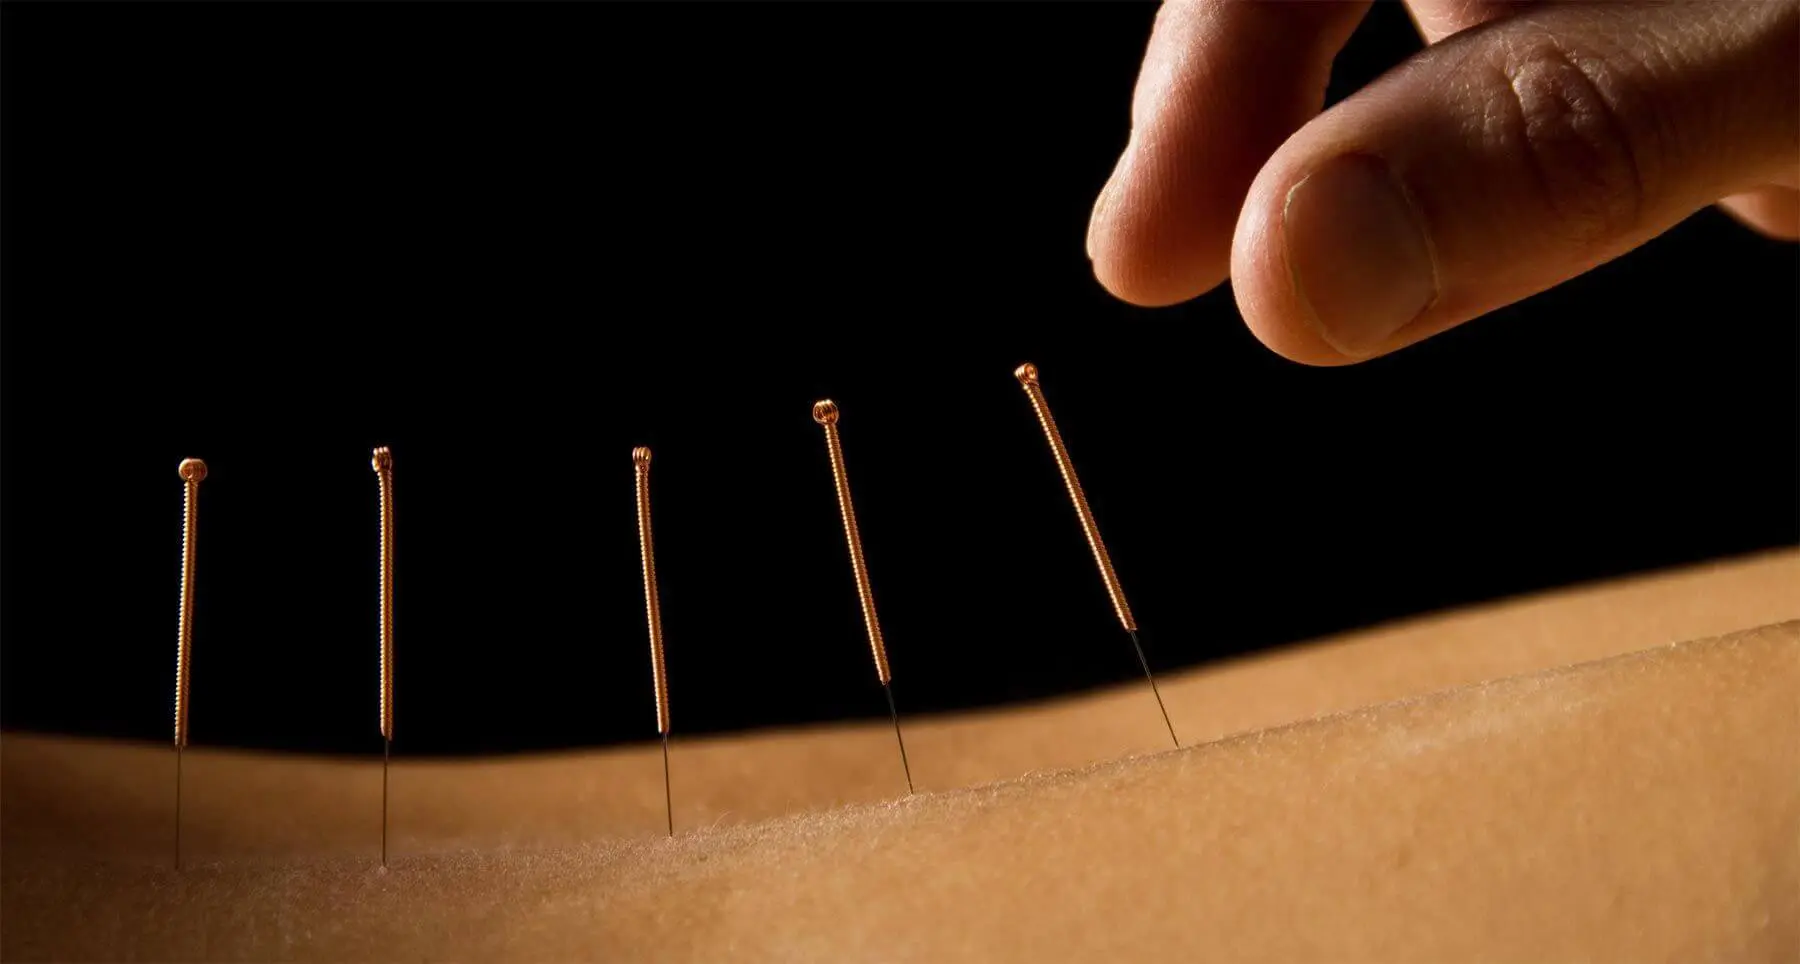

Acupuncture is a form of traditional Chinese medicine that has been used for centuries to treat these types of conditions with great success.

Our Acupuncture Pain Relief is an alternative therapy that uses needles to stimulate certain points on the body in order to heal it. It may be used in conjunction with other therapies or as a standalone treatment.

Acupuncture uses very thin needles that are inserted into the skin at specific points along energy channels in the body – called acupoints – in order to balance the flow of energy through these channels.

The needles are inserted into the skin at specific points on the body that affect muscles and joints. Some patients experience increased mobility after treatment which allows them to resume their daily activities with less discomfort. Since ancient times, acupuncture therapy has been a common practice in Eastern Asian countries.

Acupuncture is a form of Chinese Medicine that involves the insertion of needles in designated points on the body in order to stimulate the flow of energy through the meridian channels. The stimulation aids with joint and muscle function by reducing inflammation, swelling, pain, and increasing range of motion.